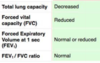

- Describe the composition, synthesis, mechanism of action and function of lung surfactant.*

- What are the three main functions of lung surfactant?

Describe the composition, synthesis, mechanism of action and function of lung surfactant.

- What are the three main functions of lung surfactant?

- • To increase pulmonary compliance.

- • To prevent atelectasis (collapse of the lung) at the end of expiration.

- • To facilitate recruitment of collapsed airways.